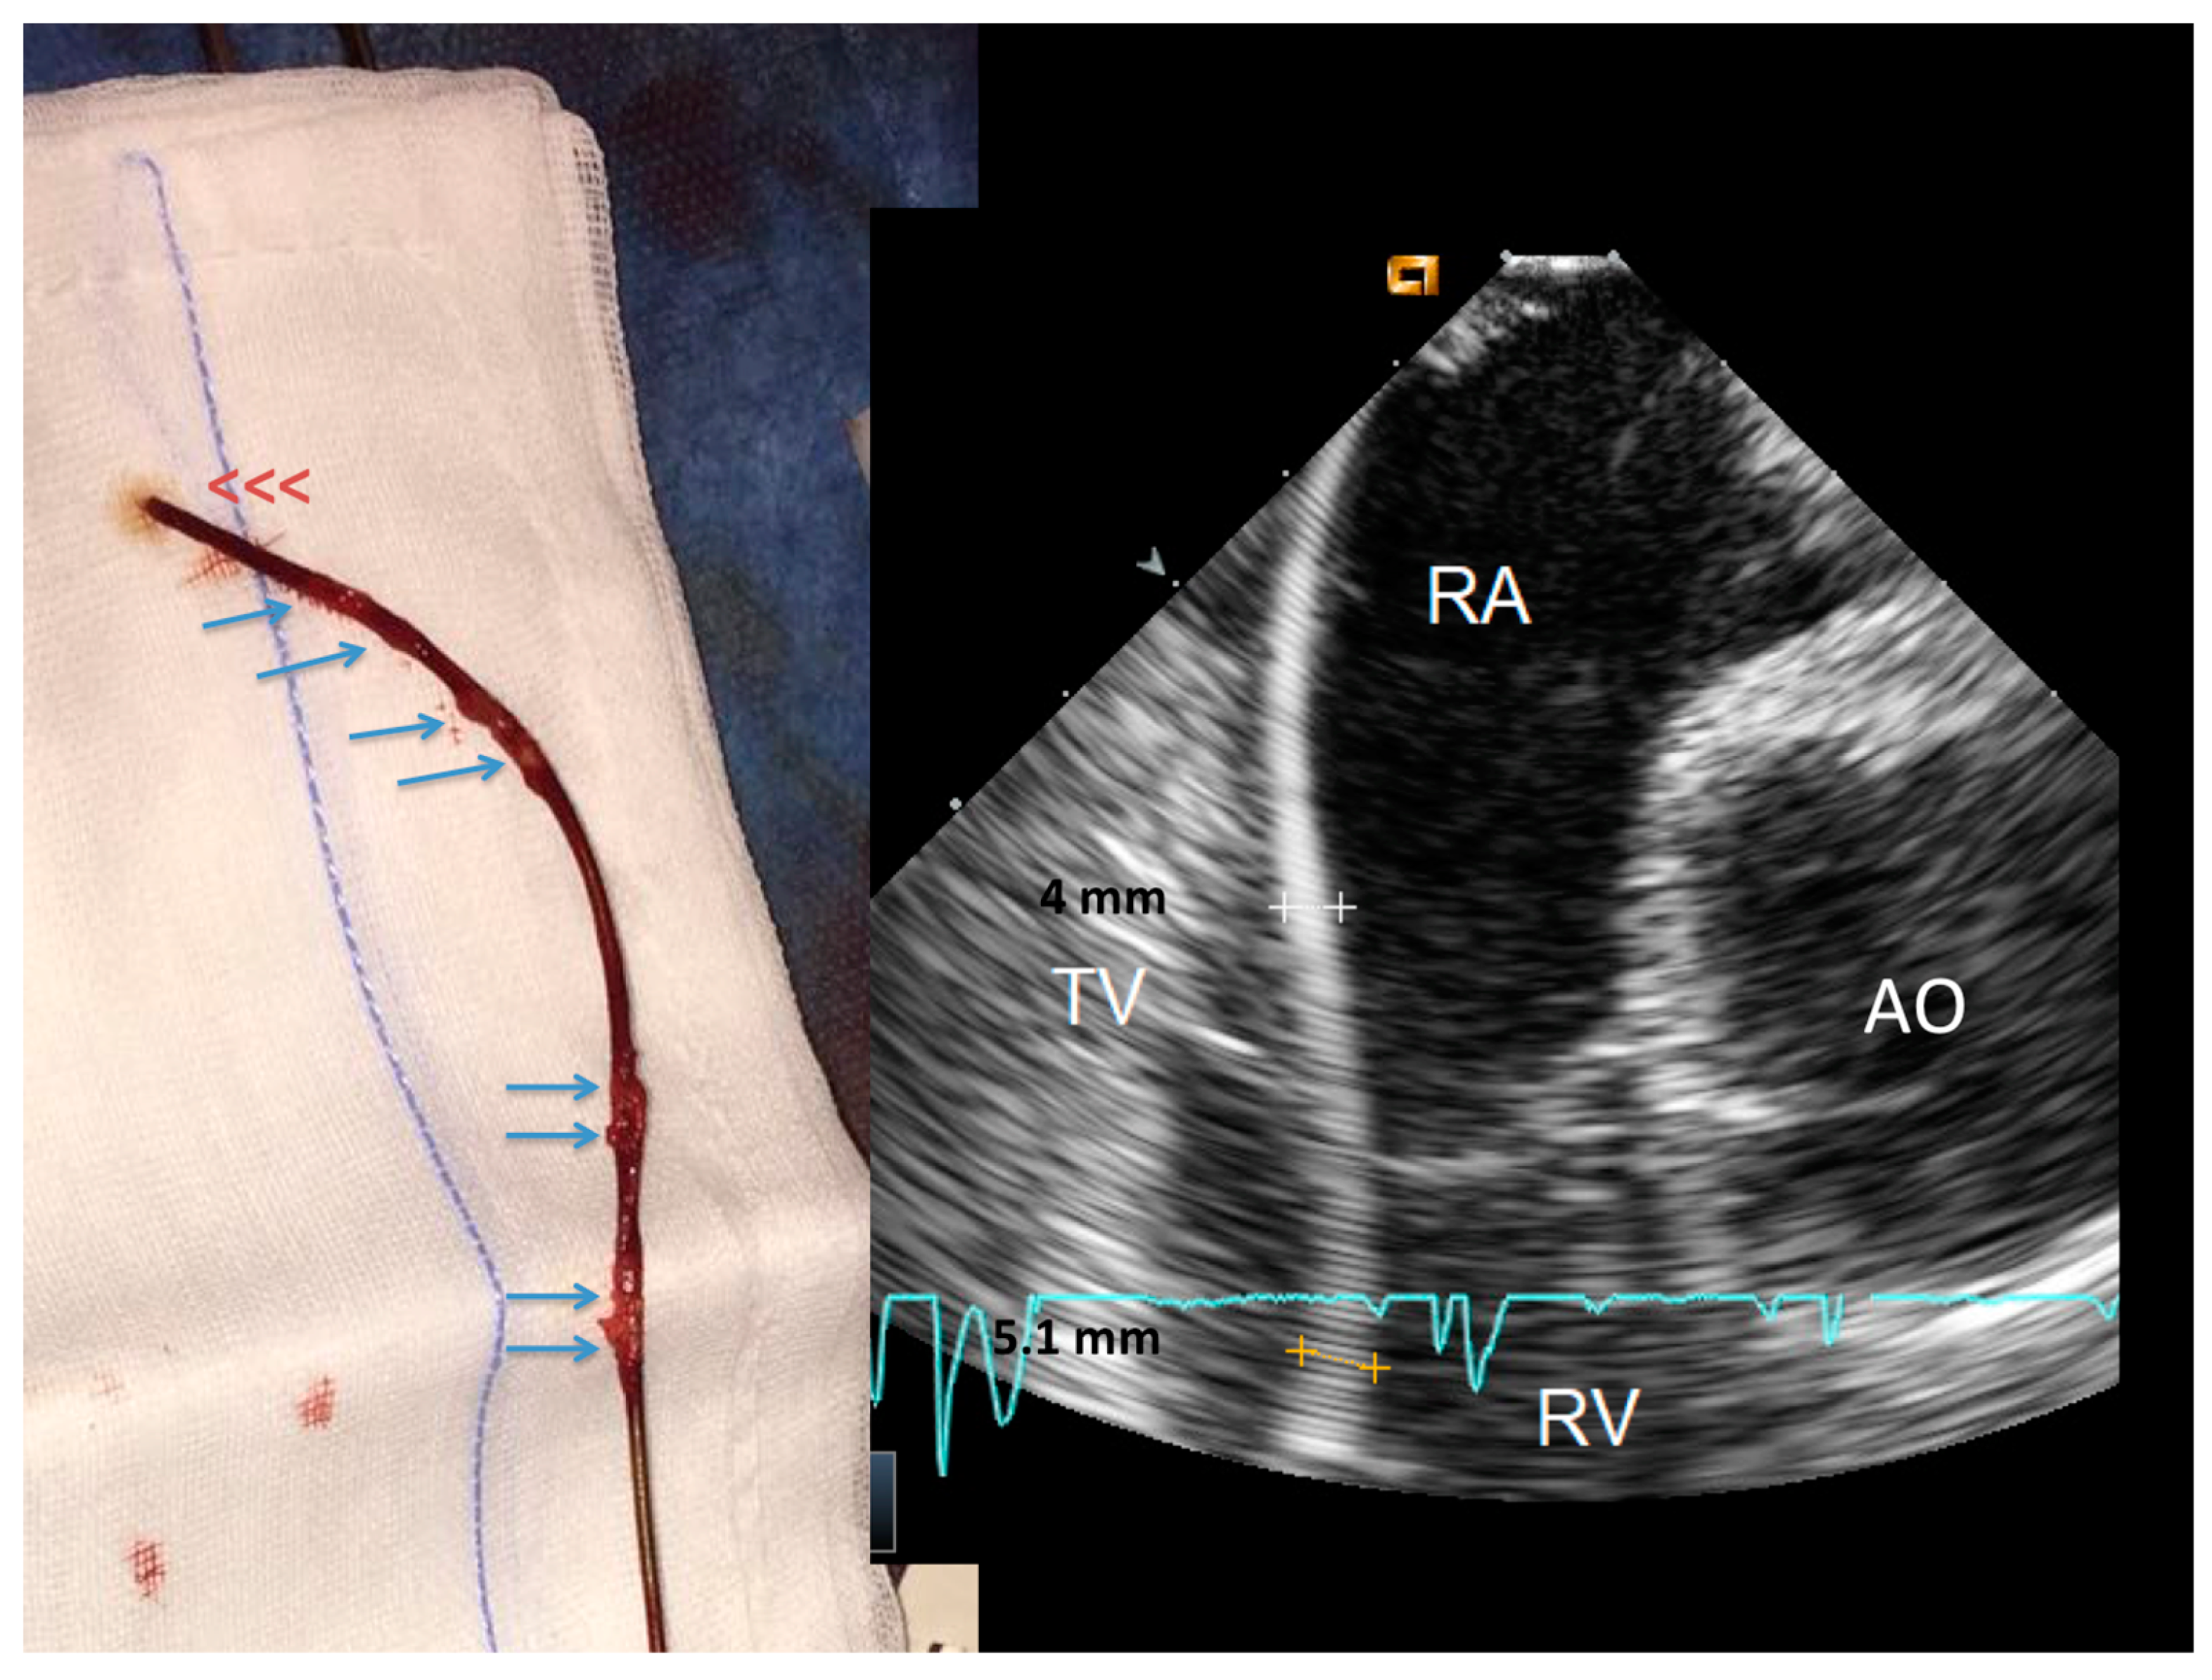

2.2.1. Before Extraction

2.2.2. After the Extraction

3.2. Post-extraction ICE

4.1. Fibrosis Involving Leads

4.2. Nature of the Ghost